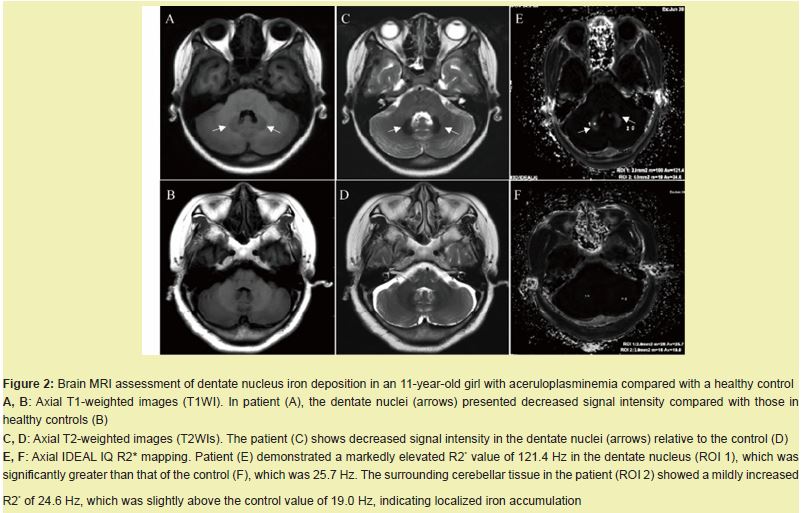

Hepatic and pancreatic iron deposition detected by CT and MRI

Abdominal CT revealed diffusely increased liver parenchymal density in the patient (95 HU), which was markedly greater than that in the healthy control (46 HU), while the pancreatic density remained comparable (49 HU vs. 41 HU) Figure 1A,B. On MRI, the patient showed diffusely decreased liver signal intensity on both T1-weighted Figure 1C,D and T2-weighted images Figure 1E,F relative to that of the control, which was consistent with iron overload. Quantitative R2* mapping by IDEAL-IQ further confirmed significant hepatic iron deposition, with a liver R2* value of 1033 Hz in the patient and 43.7 Hz in the control. A mildly elevated pancreatic iron content (157.4 Hz vs. 26.6 Hz) was also noted Figure 1G–I.

We report an 11-year-old girl with genetically confirmed aceruloplasminemia—the youngest documented to date. She presented with refractory microcytic hypochromic anemia, growth delay, and mild cognitive impairment. Laboratory studies revealed paradoxically low serum iron and markedly elevated ferritin. Whole-exome sequencing revealed a homozygous splice-site variant, c.147-2A > G, in the Ceruloplasmin Gene (CP). Pedigree analysis revealed that the parents of the affected child are carriers of the mutation.CP has six structural domains with a three-copper catalytic center, one Ca+ binding site, and one Na+ binding site, all of which are essential for its oxidative function6 and protein stability.6,7 The c.147-2A > G variant disrupts the canonical acceptor splice site. Minigene assays revealed complete skipping of exon 2 Figure 3C, 3D. Structural modeling revealed that this deletion disrupts the trinuclear copper cluster bridging domains 1 and 6, eliminates both Na⁺- and Ca²⁺-binding sites Figure 3E-H, abolishes ferroxidase activity, and explains the undetectable serum ceruloplasmin (< 20 mg/L) and pronounced early iron loading Figure 1,2.